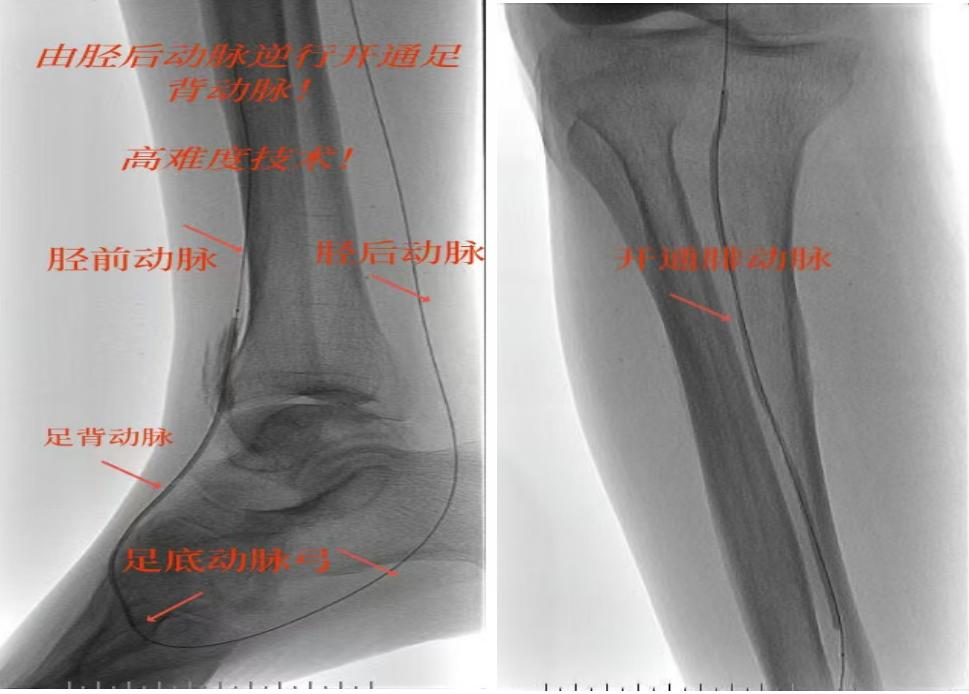

78岁男性患者,糖尿病合并高血压、脑梗塞,右足持续疼痛伴冰凉发绀3个月。入院CTA显示其右侧股浅动脉全程闭塞,膝下三支动脉均闭塞。医疗团队在局部麻醉下,再次巧妙应用“逆向开通技术”,经胫后动脉——足底弓逆向开通足背动脉及胫前动脉。术后患者右足皮温即刻回升,疼痛消失。术后结合中药外治(换药、熏洗、去腐生肌膏外敷)加速创面愈合,患者已顺利出院。

影像检查:CTA显示右侧股浅动脉全程闭塞,膝下三支动脉(胫前、胫后、腓动脉)完全闭塞。

两例患者共同凸显三大高难度治疗挑战:1.患者高龄且基础病复杂;2.血管全程多节段闭塞、钙化程度严重;3.常规顺向开通路径已被完全阻断。团队果断采用远端逆行穿刺技术,在纤细的足踝部血管建立治疗通道,实现“逆向破冰”。